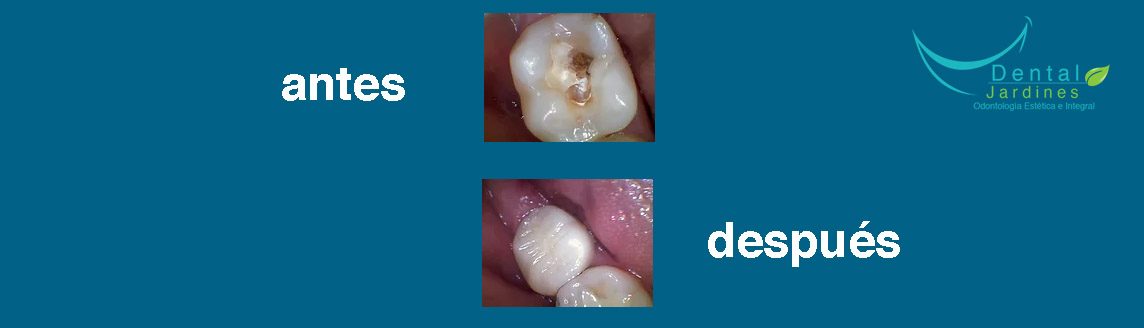

Nuestro objetivo principal es la calidad en nuestros tratamientos por lo cual te ofrecemos una consulta en la cual se te dará el tiempo suficiente para que el procedimiento tenga el mejor resultado. Nuestros tratamientos llevan un registro radiológico y fotográfico para que puedas observar el cambio en una foto de antes y después para lograr la satisfacción de nuestros pacientes.